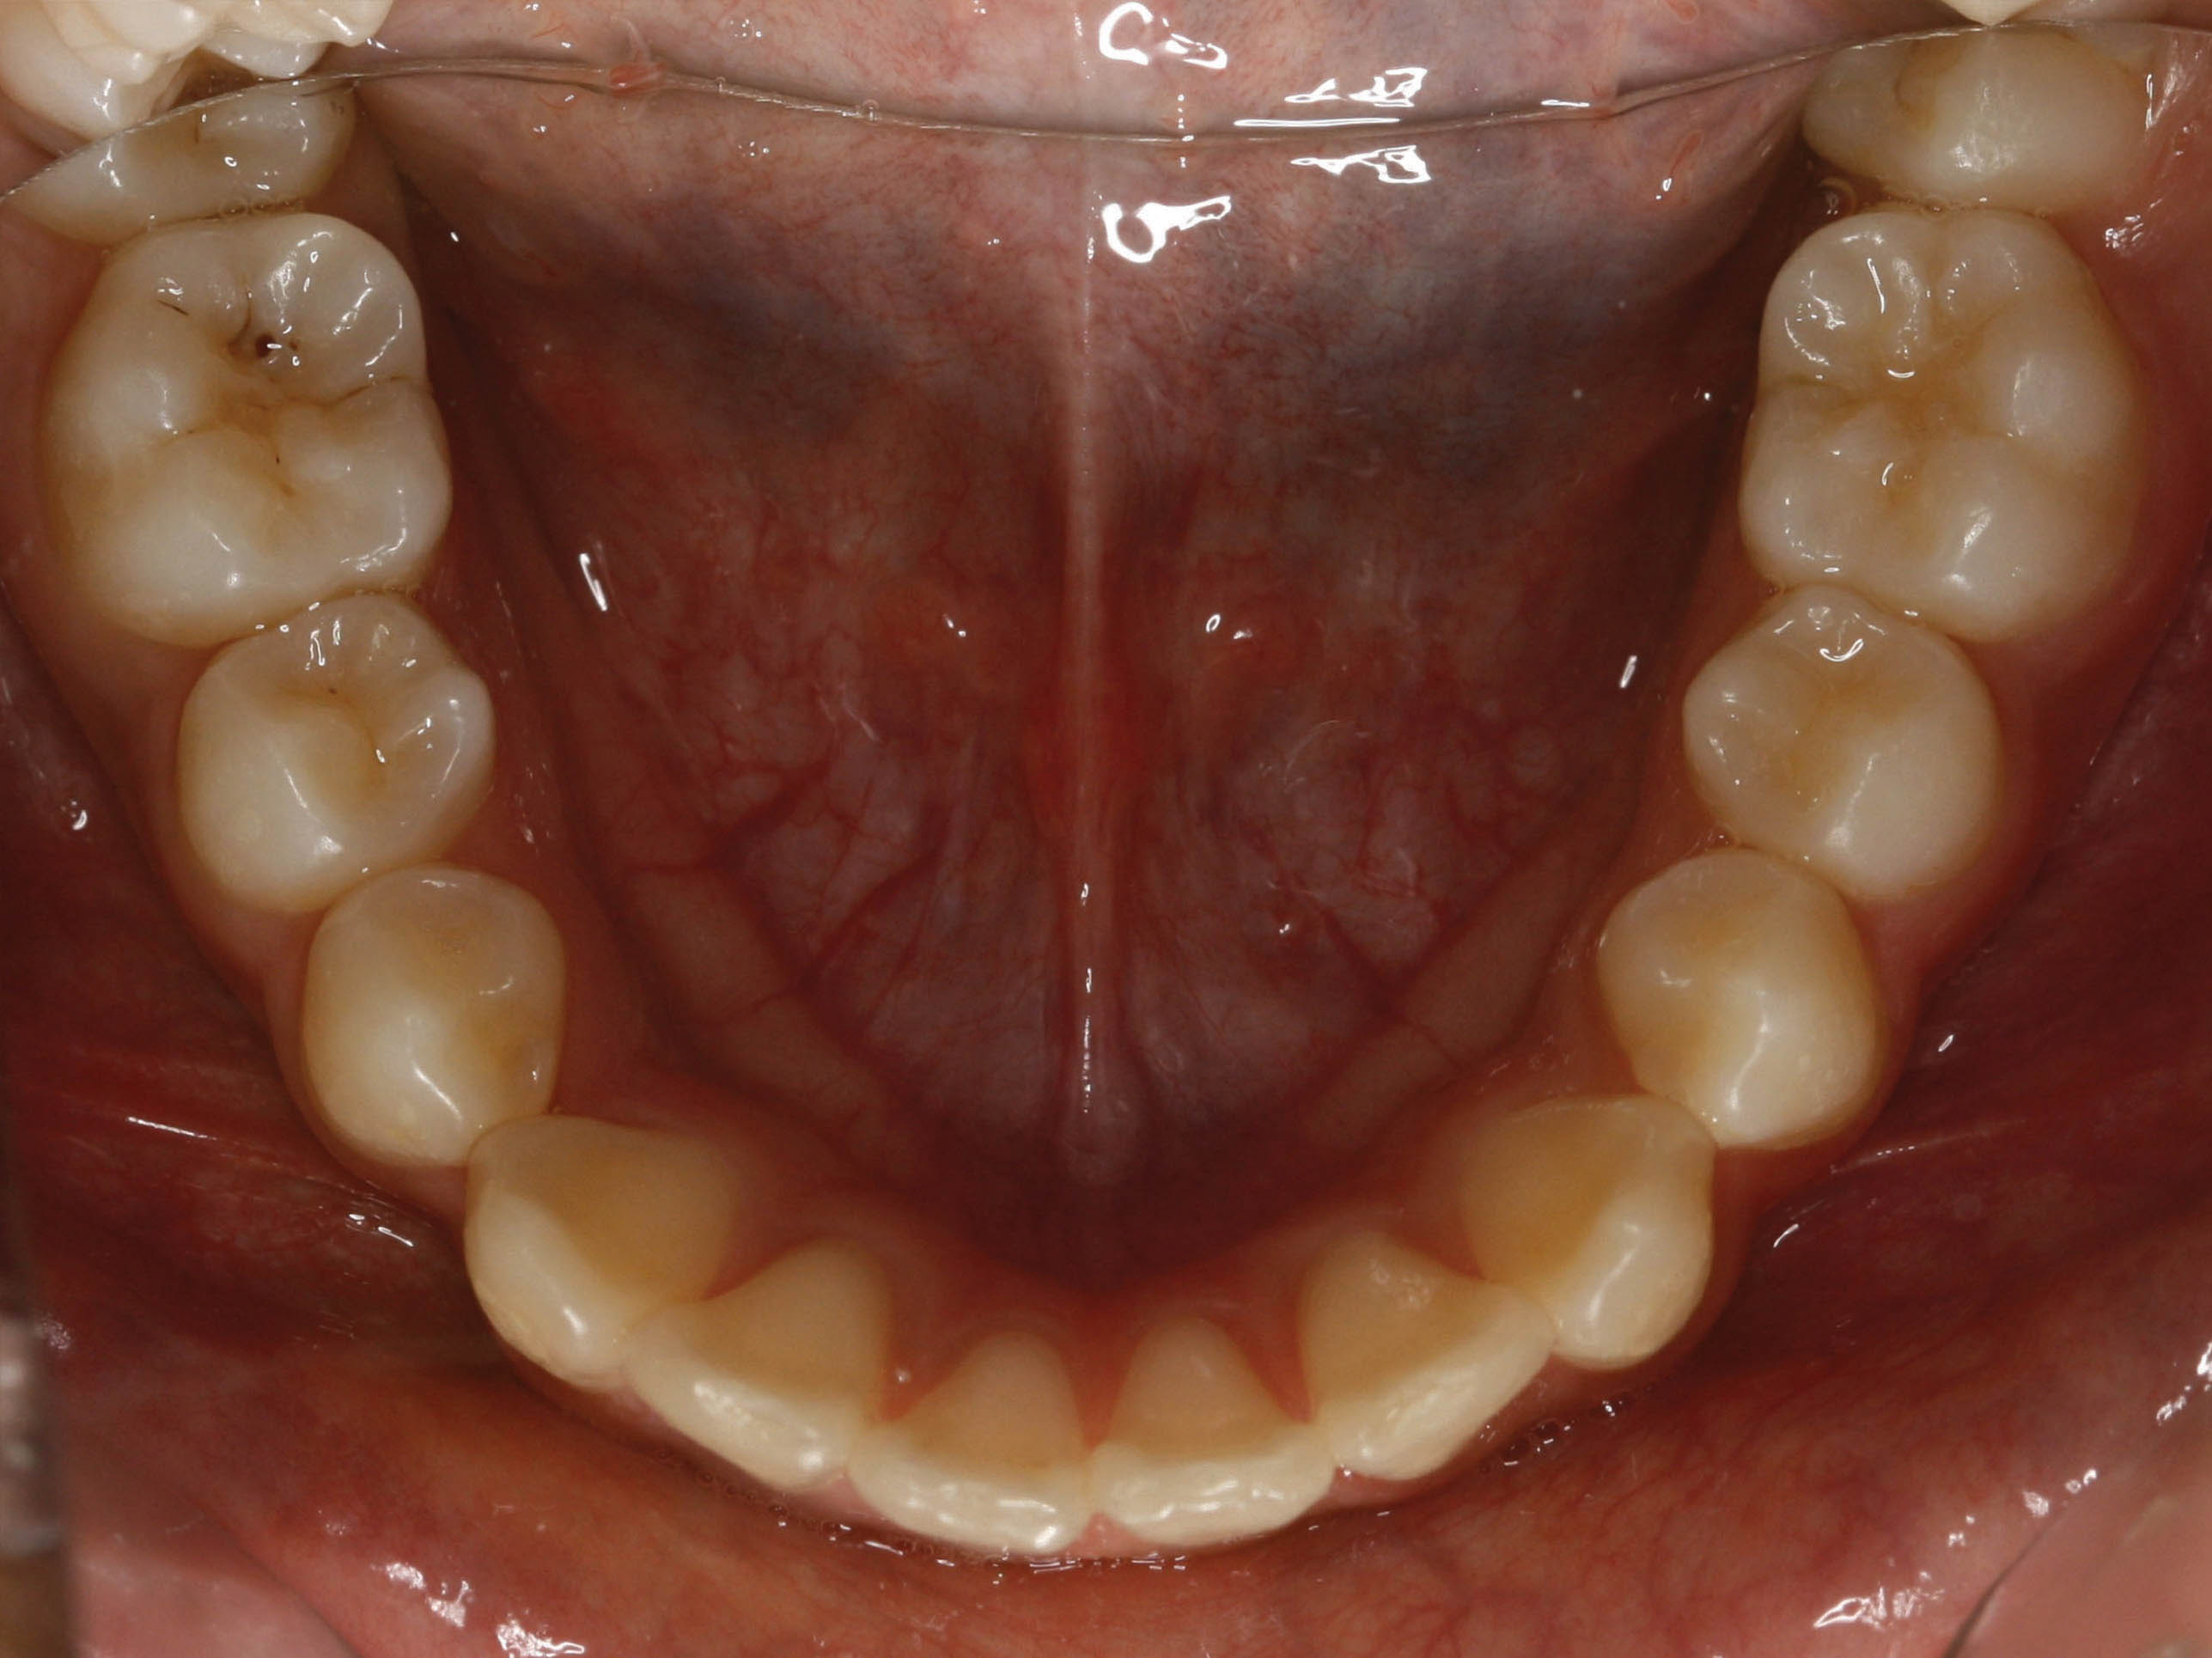

بعد از درمان